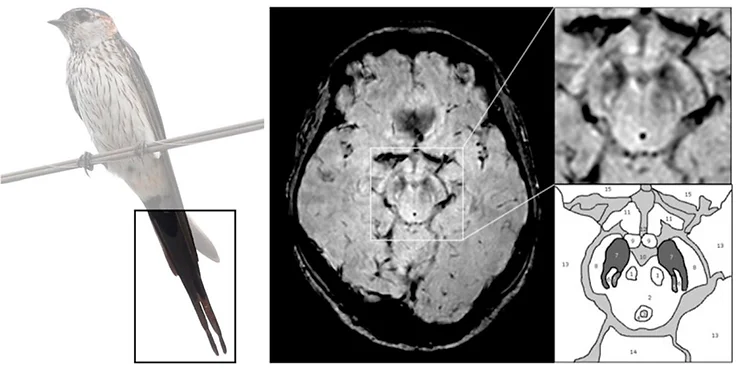

No desenvolvimento da doença, os pacientes apresentam principalmente uma neurodegeneração de sub-regiões da substância negra, como por exemplo, o nigrossoma-1. Esta região é conhecida também como “cauda da andorinha”. Sim, este nome foi dado em virtude desta pequena região cerebral possuir uma semelhança com a cauda deste pássaro! Esta estrutura possui a maior proporção de neurônios comumente afetados na doença de Parkinson.

Neste artigo, foram investigadas a viabilidade da detecção e a avaliação de alterações na cauda da andorinha usando-se ressonância magnética (3T) em 114 pacientes. Foram comparados os achados de ressonância entre pacientes com doença de Parkinson e indivíduos saudáveis. Primeiramente, a cauda da andorinha foi passível de detecção. Abaixo, uma pequena comparação gráfica da cauda de uma andorinha com a imagem gerada por ressonância magnética na substância negra, usando a técnica de imagem ponderada na susceptibilidade (SWI) em pacientes saudáveis no estudo:

Aqui, o nigrossoma-1 está localizado no terço posterior da substância negra em formato linear, de 'vírgula' ou 'cunha' e é cercado por baixa intensidade de sinal em SWI anterior e lateralmente (pars compacta) e medialmente por baixo sinal no leminísco medial (fig. 1). O Nigrossoma-1 e suas estruturas circundantes possuem semelhança com a cauda de uma andorinha na imagem axial (HR-SWI).